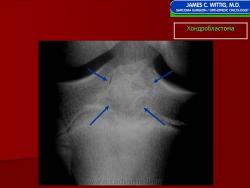

Рентгенологически хондробластома представляет собой сравнительно большой (2-4 см) очаг округлой формы, четко отграниченный от окружающей кости склеротической каймой. На фоне очага в большинстве случаев, но не обязательно определяются плотные включения, напоминающие хлопья ваты.

Рентгенологическая картина. Хондробластома выглядит как небольшой, от 3 до 6 см литический очаг, центрально или эксцентрично расположенный, с четкими контурами, занимающий около половины площади эпифизарной зоны. Хондробластома плоских костей и мелких трубчатых костей больших размеров, может сопровождаться припухлостью мягких тканей, вздутием кости и периостальной реакцией. Распространение процесса на метафизарную зону встречается часто.